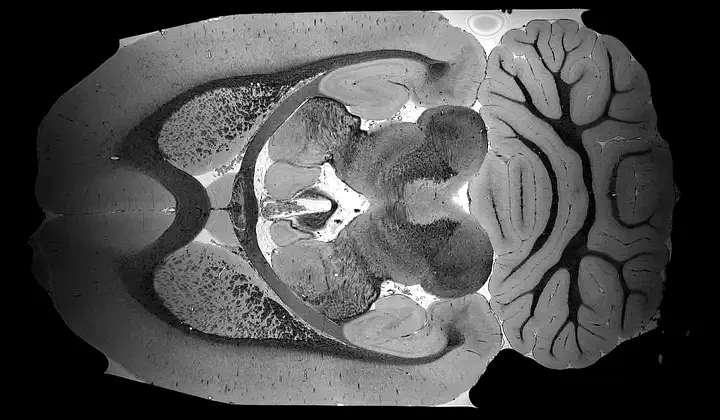

Biomedical imaging team-science

We are pleased to offer our expertise in imaging sciences to our interdisciplinary collaborators who are engaged in various team-science efforts. Our services range from grant writing support to data acquisition and analysis, all the way through to manuscript preparation. For our collaborators at the University of Buffalo, we are proud to be able to design imaging studies at the Center for Biomedical Imaging, implement and optimize 3T MRI, 9.4T MRI, and PET research imaging protocols, and develop image analysis strategies. We look forward to continuing to provide our support to our valued collaborators.